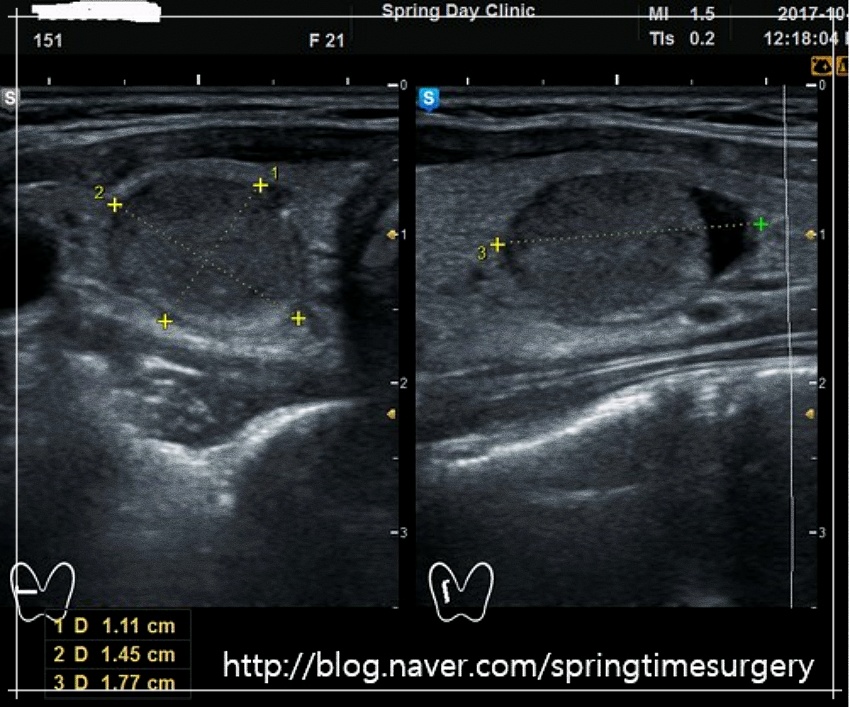

수술적 치료를 통해 모두 제거할 필요는 없지만 정기적인 추적관찰을 통해 결절 추이를 보면서 치료방법을 결정하게 됩니다. 만약 양성종양의 크기가 지속적으로 커지거나 숫자가 계속 늘어날 경우 주변 조직을 압박해 숨이 차거나 음식을 삼키기 어려운 경우, 이물감이 느껴지는 경우 등이 있다면 갑상선 고주파 열치료와 같은 비수술적 치료를 할 수 있습니다.

결절 부위에 작은 바늘을 삽입한 후 고주파열을 전달하여 결절을 구성하고 있는 조직을 괴사시키는 치료를 말합니다. 초음파로 결절을 보면서 바늘을 넣어 고주파 에너지를 전달하기 때문에 주변 정상 조직을 손상시키지 않는 것은 물론 시술 시간이 짧아 흉터나 부작용 발생률이 적다는 장점이 있습니다.